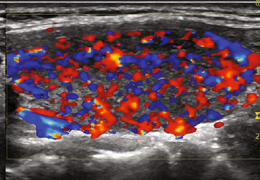

Uniformly enlarged thyroid

Hypoechoic

Heterogeneous echotexture

Hypervascular (‘Thyroid inferno’)

Differential = Hashimoto’s Thyroiditis